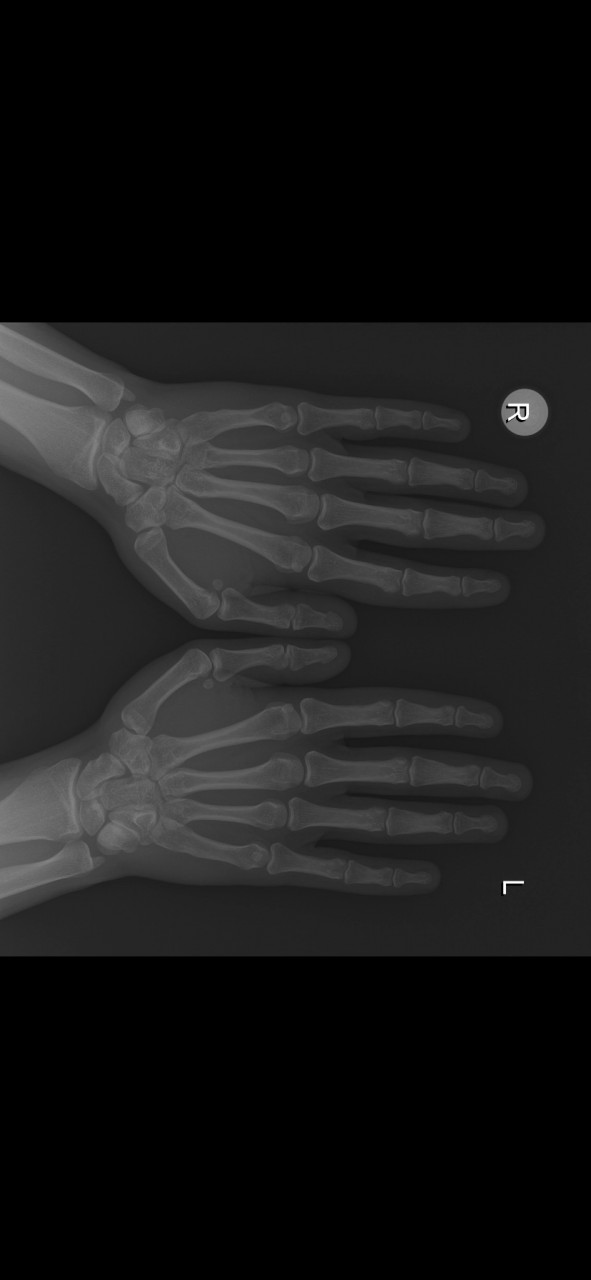

Добрый день. Мне 19. Рост 171. Рост отца 171. Рост матери 165. Смогу ли еще подрасти? Если да, то насколько примерно? Недавно делал рентген, прикрепляю.